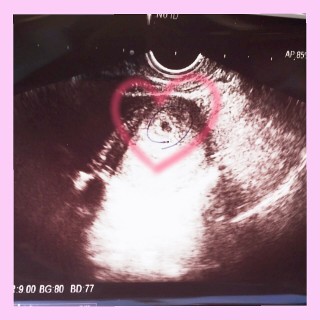

初めてドキドキしながら行った産婦人科! パパと一緒に行って、写真を見せたら うるうるしながら可愛いって言ってもらえて幸せだった! いいママ、パパになれるように頑張りたい(^^) 頑張ってこの子を幸せにしたいです! 元気に育ってくれよ~~